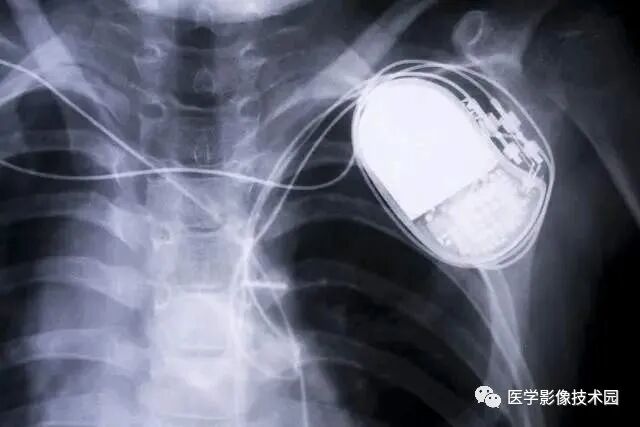

(1)心脏起博器、人工耳蜗患者;